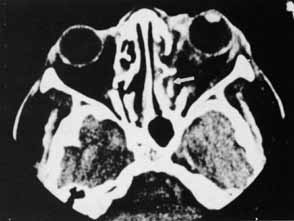

The diagnosis of orbital foreign bodies may be elusive, and clinical signs often are minimal. A detailed history about the circumstances of the injury is important, and it is especially important to suspect the diagnosis. Often, the clinical signs appear trivial. Reconstructing the circumstances of the injury may provide information about the foreign material and size of the body. The relative velocity of the object may help to predict the extent of the injury. Small objects traveling at high speeds are more likely to penetrate the globe before entering the orbit, whereas objects of slower velocity, such as sticks or twigs, are more likely to spare the globe (Fig. 17).21

Fig. 17 Piece of a sled embedded in the orbit. The globe was not injured.